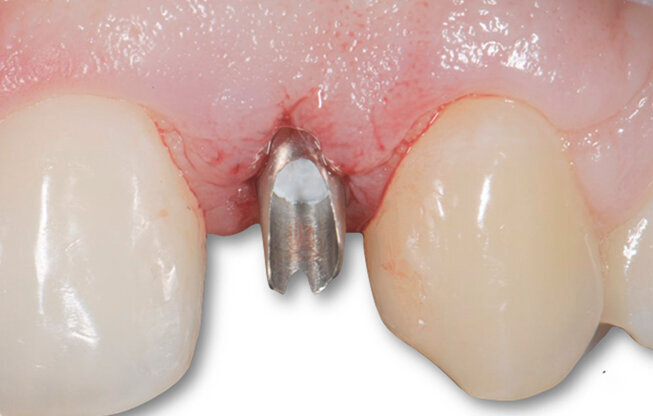

Fig. 5 - Moncone in posizione.

La mascherina viene utilizzata nella fase intermedia post-operatoria come supporto estetico coprendo l’area edentula. La fase protesica finalizza il caso nel rispetto dei tessuti parodontali.

A guarigione dei tessuti molli è stata rilevata l’impronta di posizione per la realizzazione dell’abutment definitivo e la costruzione dei provvisori, sia per la corona su impianto dell’elemento 22 sia la veneer dell’elemento 12. Eseguito un adeguato condizionamento dei tessuti molli, sono state poi posizionate a distanza di 10 mesi la corona definitiva a livello di elemento 22 in zirconia integrale a veneer in ceramica a livello di elemento 12 (Figg. 5-6c).